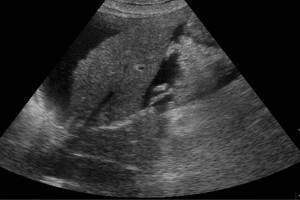

Diplomados en Ultrasonografía

Hola, conoce nuestros diplomados.